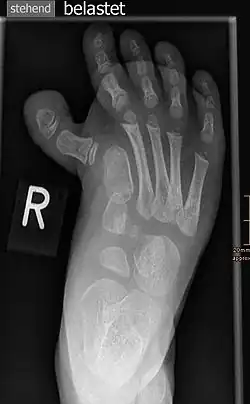

Hallux varus

Der Hallux varus ist eine Varus-Abweichung der Großzehe im Großzehengrundgelenk (Art. metatarsophalangea prima), die damit nach innen, medialwärts zeigt. Diese sehr seltene Deformität ist das Gegenteil eines Hallux valgus und in der Mehrzahl der Fälle seltene Komplikation einer Hallux-valgus-Korrekturoperation. Andere Fälle sind angeboren oder posttraumatisch bedingt.